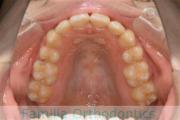

No.23V-061

- 主な症状:

- 叢生

- その他の症状:

- 上下顎前突

- 年齢:

- 23歳

- 性別:

- 女性

- 抜歯部位

- 上:

- 44

- 下:

- 主な使用装置:

- FEA 022

- 治療にかかった費用:

- 88万円

でこぼこを綺麗に並べたいということで来院されました。上下左右から小臼歯を抜歯して、マルチブラケット法を2年半、30回程度通院していただいて行いました。

かなり強い叢生(でこぼこ、凹凸、ガタガタ)のため、保定をしっかりしないと後戻りのリスクが高いケースといえます。

- ≫治療前

-

上顎

下顎

前歯の関係など

右側

正面

左側

- ≫治療後